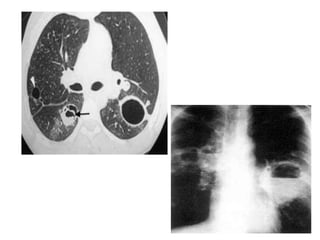

STADE EVOLUTIF DU khp

• Stade I : KH non rompu ( ds 50 à 70%) ,

asymptomatique

Opacité homogène ronde ,ovalaire de tonalité

hydrique

A contours nets comme tracé au compas

En boule de canon , ou parfois bilobée en

brioche,réniforme, polycyclique variable avec

le diamètre (hémithorax opaque avec culs de

sac costodiaphrarmatique libre)

Opacités multiples,parfois lachée de ballon

• Stade II , retrouvé ds 11,2% des cas,

Fissuration, hémoptysie, :

Ménisque gazeux situé au pole supérieur de

l’opacité entre la paroi externe du kyste et la

paroi interne du périkyste.

Image de pneumokyste

Évolution: surinfection espace périkystique